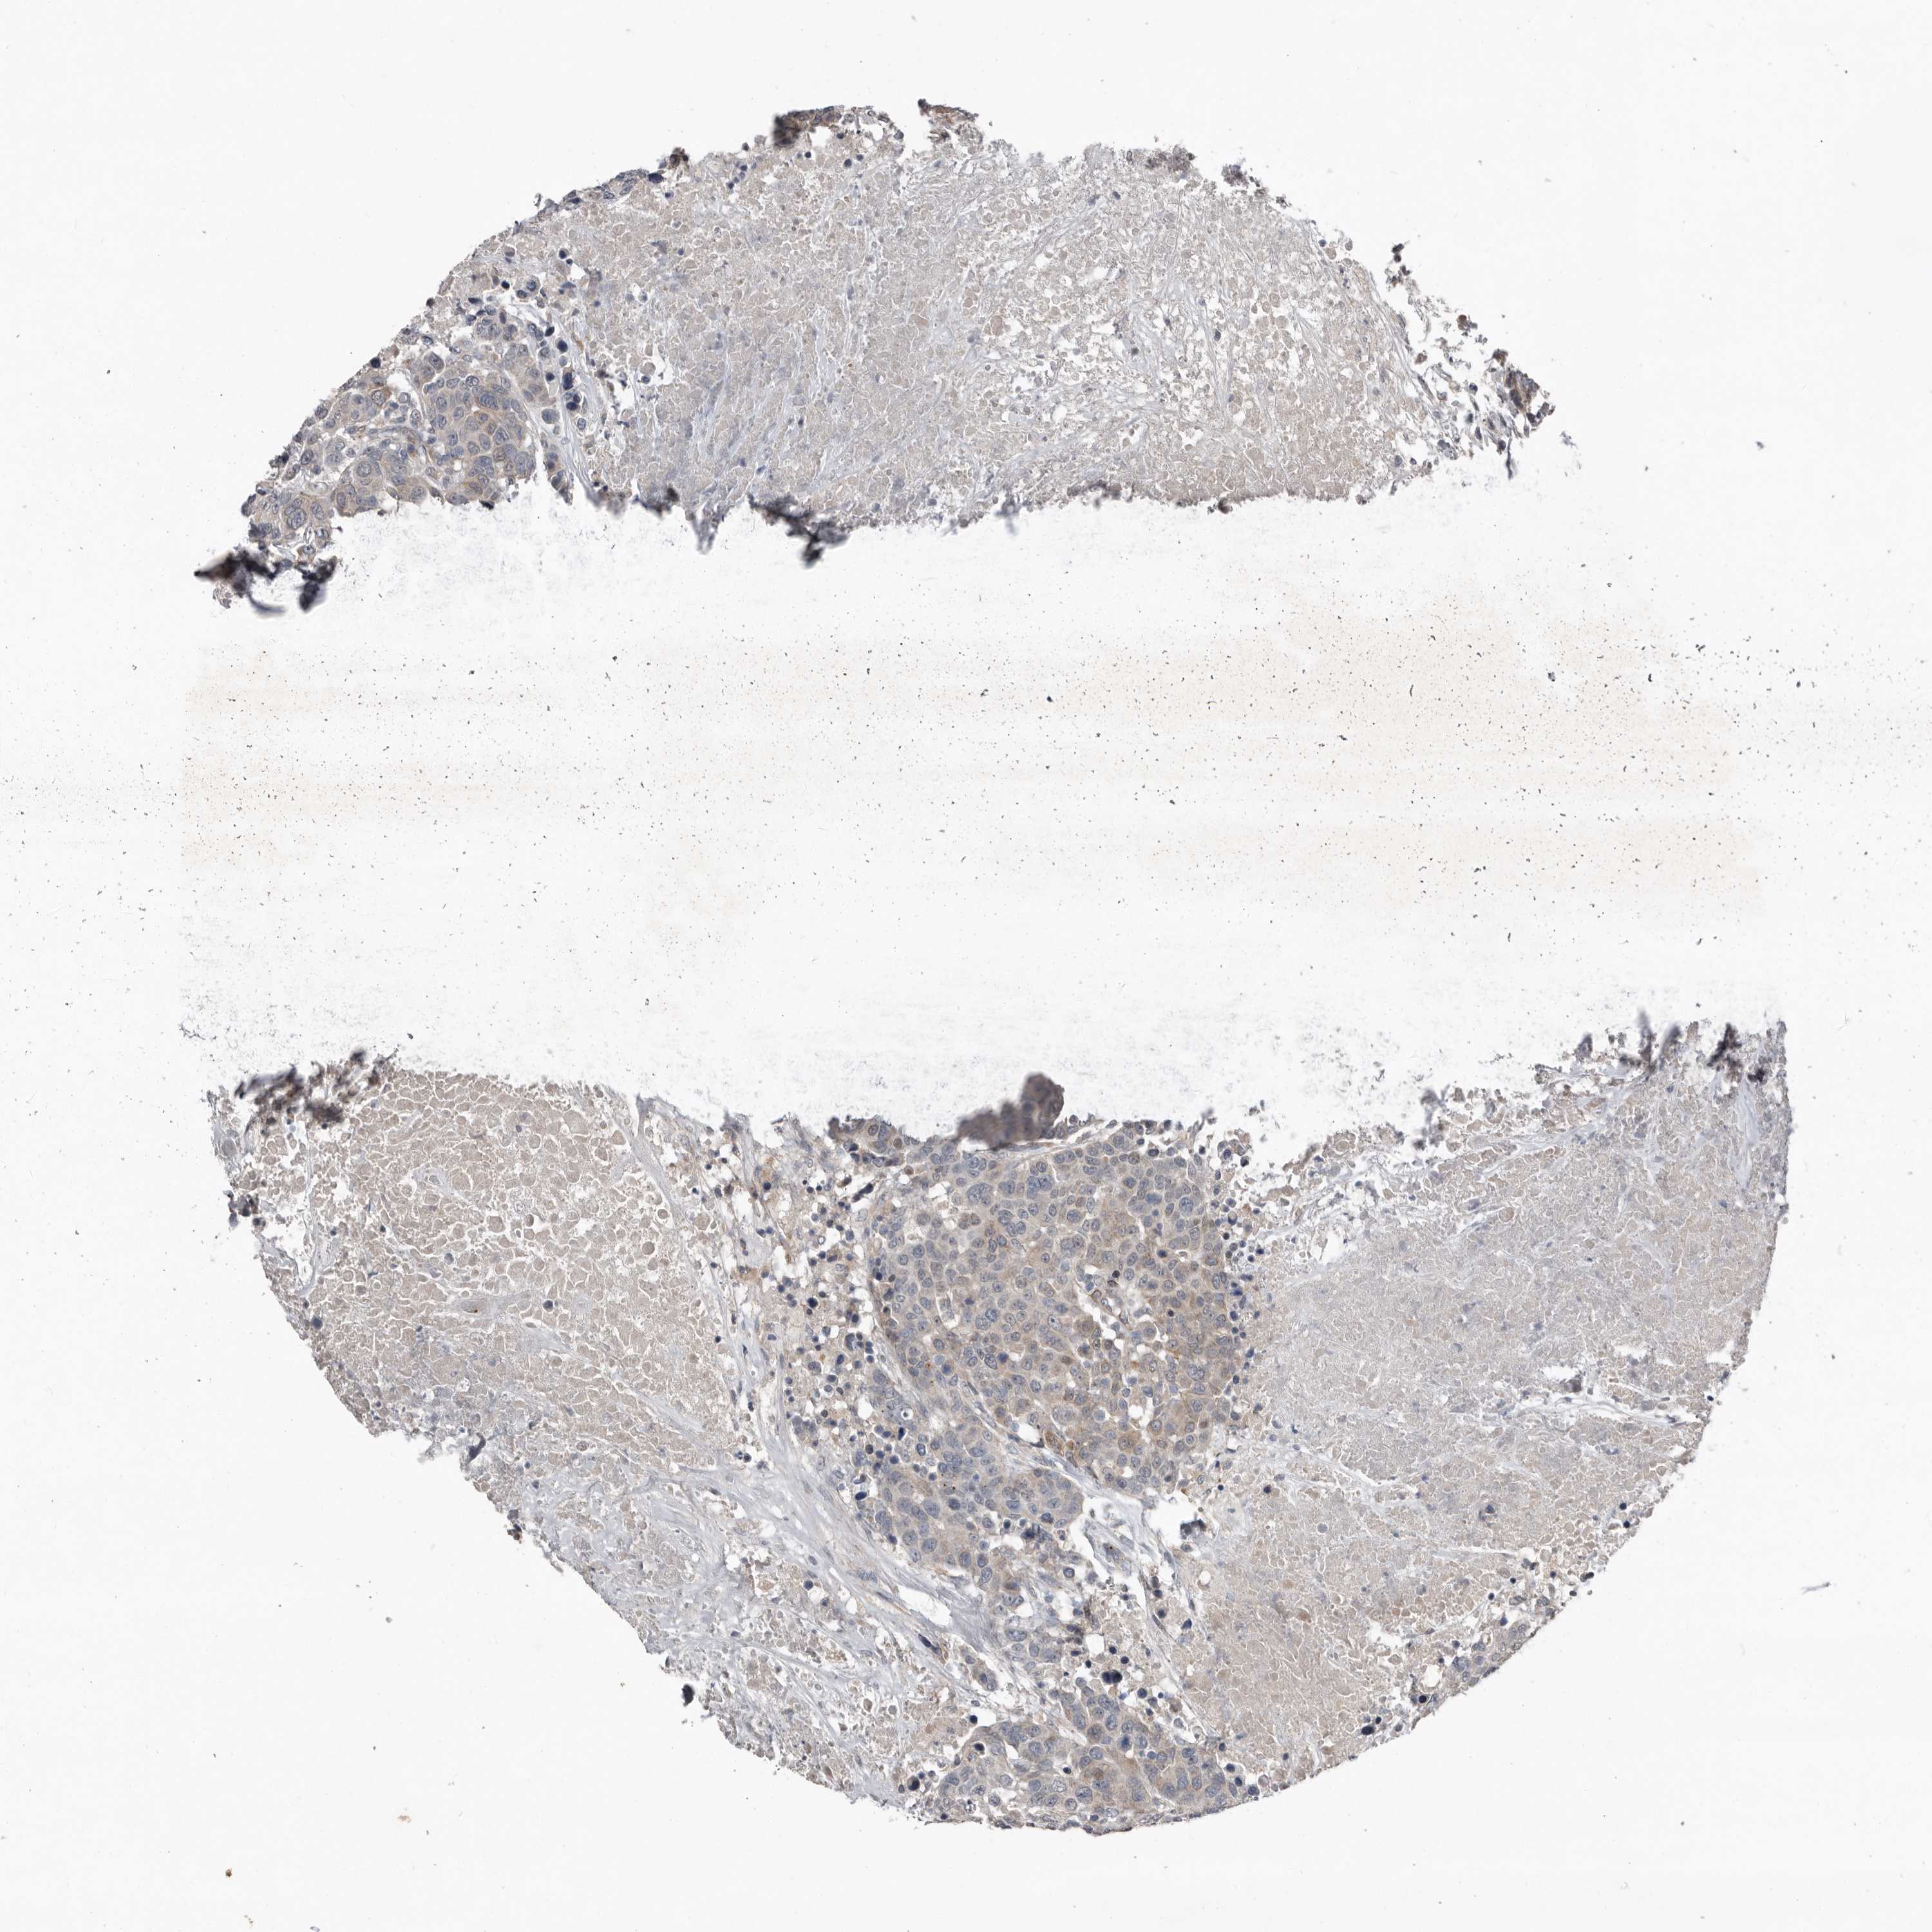

CANCER BREAST CANCER Show tissue menu

BRCA TCGA BRCA VALIDATION PROTEIN EXPRESSION